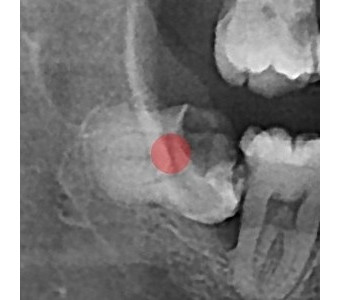

결과로 증명합니다.

국제모아치과의

실제 임상 증례